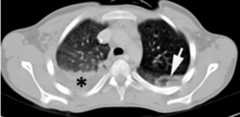

Chest CT showing a hemothorax in the right lung

Arrow indicates a lung contusion and a collection of fluid thought to be a hemothorax.